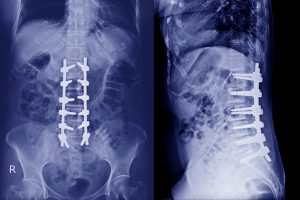

If further testing is required, the doctor will prescribe diagnostic tests. These tests include imaging, such as MRI or CT scan, and a discogram.

In some cases, the recommended treatment is spinal manipulation by a chiropractor. When severe pain is present, doctors often prescribe painkillers. The worst case scenario is spinal surgery after all other options have been exhausted.